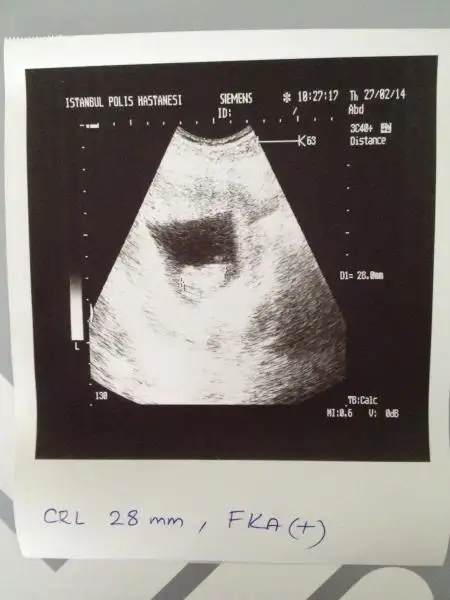

Gurbet ablam arkadasimin bebegi ALLA RIZASI ICIN BI BAKSAN KIZ MI ERKE MI? ustteki iki resim bugunku goruntuler en alttaki 6 hatalikken